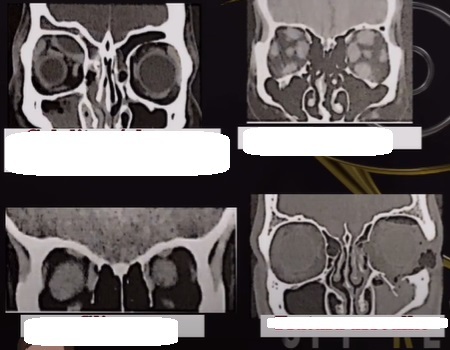

Lesão fusiforme na topografia do nervo óptico com a tomografia mostrando ausência de calcificação? Devemos lembrar do glioma de nervo óptico

clinica de glioma

essa lamina é do glioma

o que achamos nele